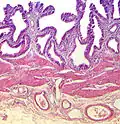

| Tinción | Tipo | Características | Uso | Ejemplo |

|---|---|---|---|---|

| Hematoxilina | Básica / Acidofílica | Tiñe núcleos, ácidos nucleicos y estructuras basofílicas (mitocondrias y ribosomas) en azul. | Tinción histológica general |

|

| Eosina | Ácida / Basofílica | Tiñe proteínas y estructuras con afinidad por los ácidos en diferentes tonos de rojo | Tinción histológica general |

| Tinción hematoxilina-eosina | Bicomponente Anfifílica |

Tinción histológica general |

| Tinción hemalumbre-eosina | Similar a la tinción H&E con colores más marcados y definidos | Tinción histológica general |

| |